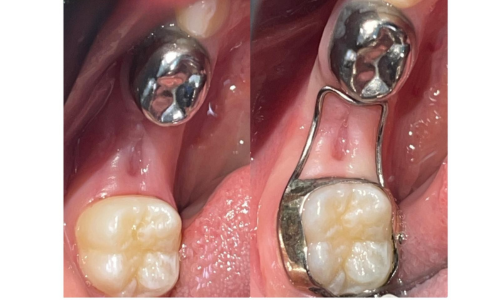

علاج الاطفال